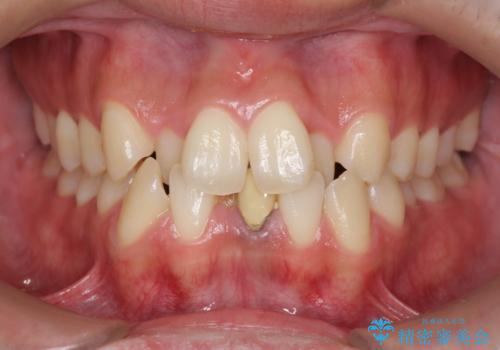

- 前歯のガタガタを主訴に来院。

下の前歯は一本保険治療での被せ物になっており、変色していました。

・神経のない下の前歯を残す

・神経のない歯を抜いてしまって、天然歯で閉じる

のプランを提案し、神経のない前歯を抜く選択をされました。

下の前歯が3本になり奇数になることで、上下の真ん中は一致しませんが、そこまで目立たないと思います。